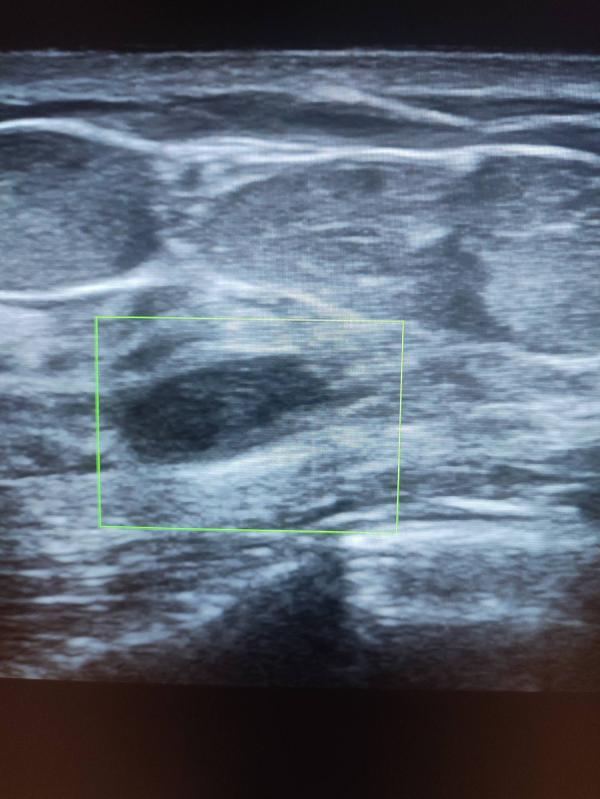

Добрый день девочки ! Хочу рассказать случай из практики: вчера у меня на приеме была девочка , возраст 31 год, планово готовилась на ЭКО, замужем 3 года! При УЗИ молочных желез было выявлено вот такие образования- точнее сказать рак левой молочной железы! В данном случае ни о какой беременности речи быть не может, тем более ЭКО ! Здесь длительное лечение , с последующей долгой реабилитацией! Самое интересное ,что она уплотнения отмечала давно , но к врачу не ходила ! (((